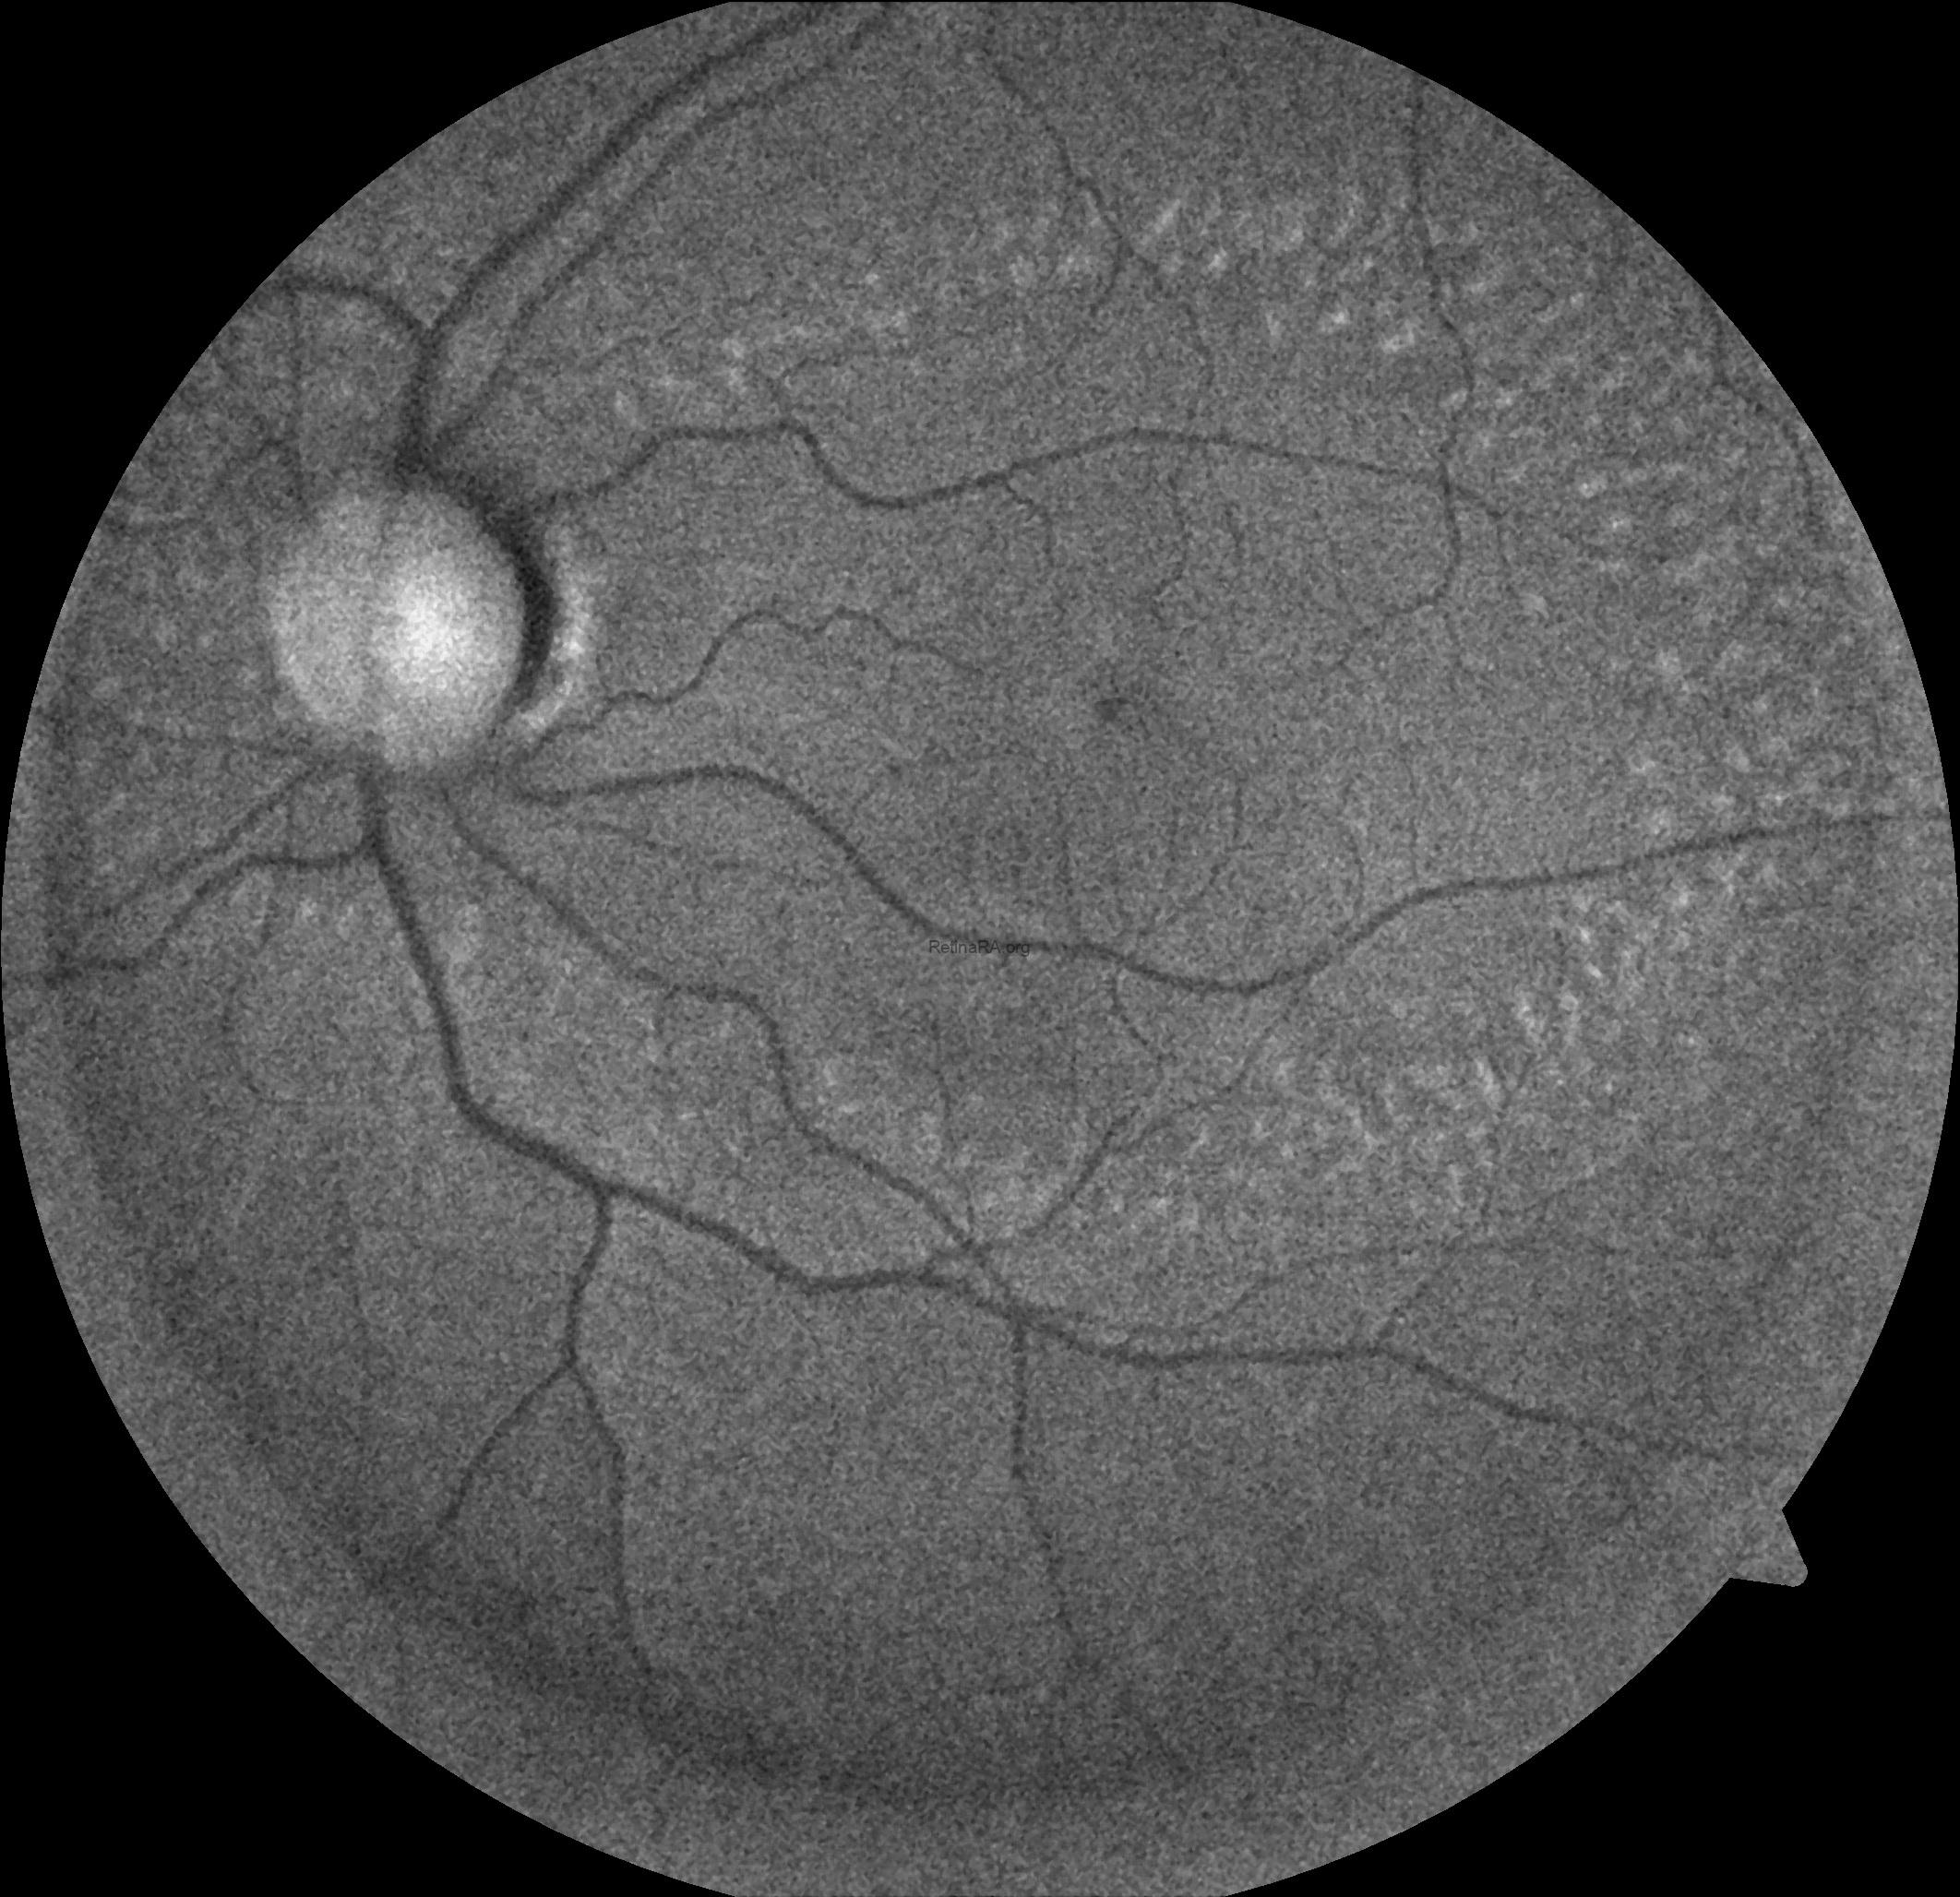

Optical coherence tomography (OCT) provides valuable structural information in fundus albipunctatus. OCT imaging typically demonstrates focal hyperreflective material originating from the RPE and projecting into the outer retinal layers, correlating with the punctate lesions seen on fundus examination. On fundus autofluorescence imaging, a diffusely reduced background autofluorescence is commonly observed, reflecting impaired retinoid metabolism and RPE dysfunction related to disruption of the visual cycle.